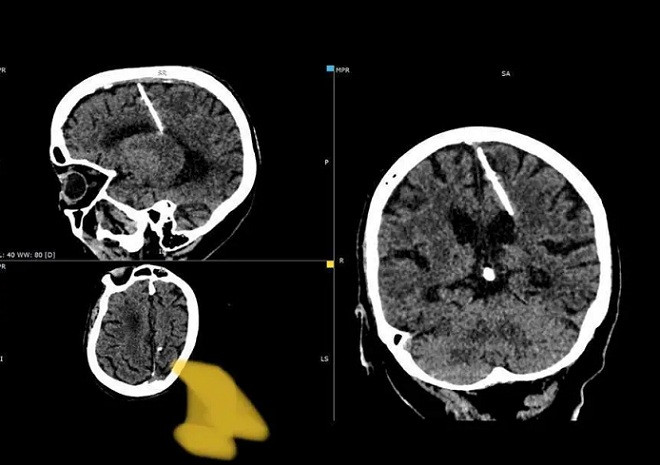

05/10/2023 17:44Cây kim trong não cụ bà 80 năm và câu chuyện bố mẹ cố giết con thời Thế chiến 2

Các bác sĩ trên đảo Sakhalin của Nga kết luận, chiếc kim có thể là bằng chứng cho nỗ lực bất thành của chính cha mẹ cụ bà, khi họ cố giết con trong Thế chiến thứ Hai.

“Những vụ việc như này không phải là hiếm trong những năm đói kém. Một cây kim mỏng sẽ được đâm vào thóp của trẻ sơ sinh để làm tổn thương não. Thóp nhanh chóng đóng lại, che đậy bằng chứng phạm tội của bố mẹ, và đứa trẻ sau đó qua đời”, tờ New York Post dẫn chia sẻ trên kênh Telegram của Sở Y tế Sakhalin.

Cũng theo Sở Y tế Sakhalin, trong trường hợp này, cây kim dài gần 3cm đã đâm vào thùy đỉnh trái, nhưng không tạo ra tác dụng như mong muốn. Bà lão đã chung sống với cây kim mà không hề hay biết trong suốt 80 năm qua. Bà cũng chưa từng phàn nàn về việc bị đau đầu.

Mọi chuyện chỉ được phát hiện, khi bà lão đi khám và chụp CT. Các bác sĩ quyết định sẽ không rút cây kim vì lo sợ nó có thể gây ảnh hướng xấu tới bệnh nhân.

Giới chức y tế địa phương khẳng định sức khỏe của cụ bà không gặp nguy hiểm, và bệnh nhân “đang được bác sĩ điều trị theo dõi".